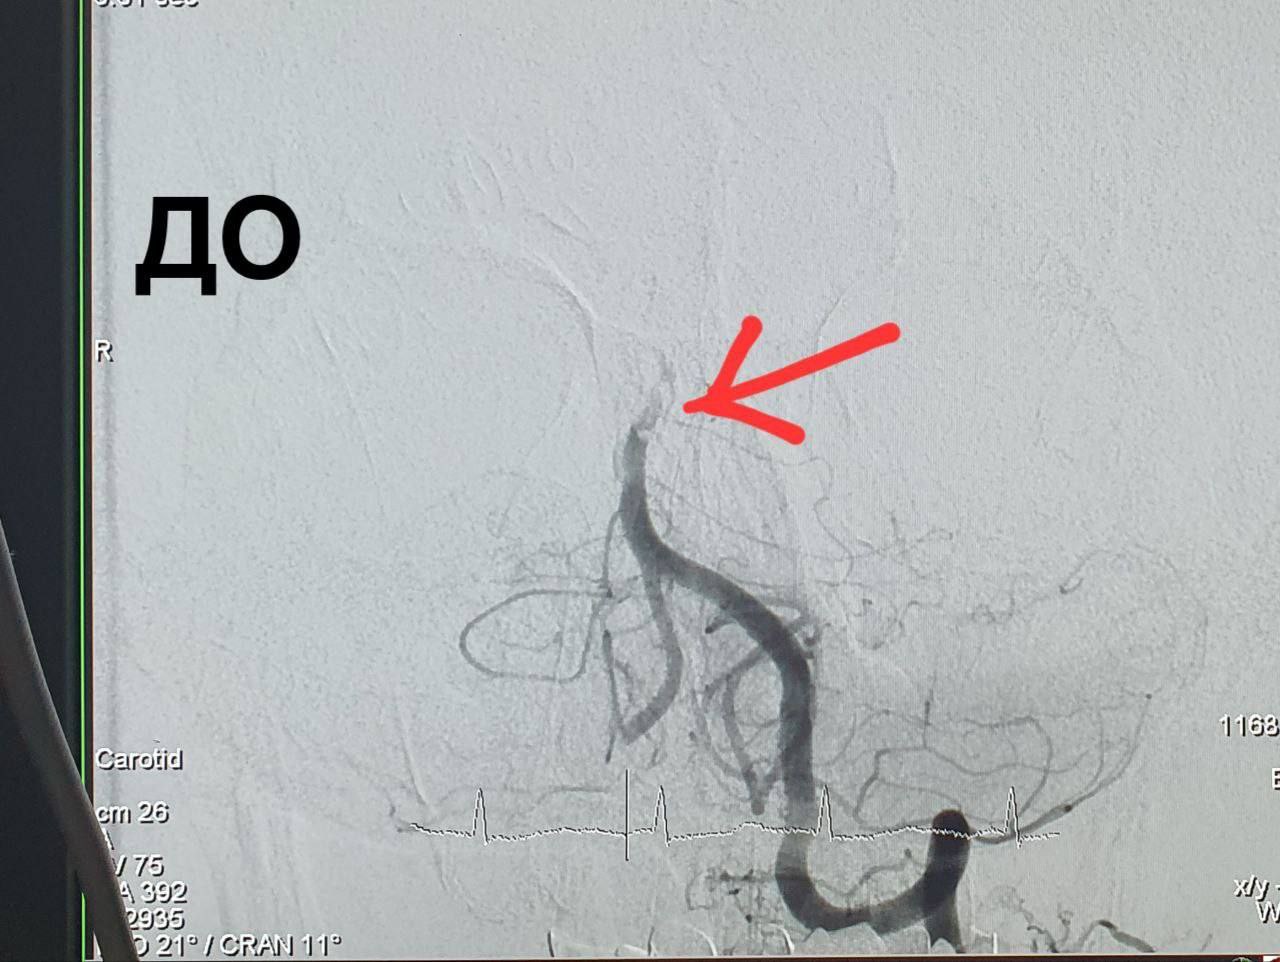

— Пациент в крайне тяжелом состоянии на аппарате искусственной вентиляции легких транспортирован в нашу больницу. Мужчине выполнена ангиография, при которой выявлена окклюзия (закупорка) базилярной артерии. Одномоментно хирургами отделения рентген-хирургических методов диагностики и лечения выполнена операция — реканализация, аспирационная тромбэкстракция из базилярной артерии. Из артерии извлечено большое количество тромбов, ее проходимость полностью восстановлена, — рассказал Алексей Демин.

Реканализация, аспирационная тромбэкстракция из базилярной артерии» потребовалась 59-летнему мужчине. Пациент находился на работе. Он пожаловался коллегам на головную боль и потерял сознание. Сотрудники вызвали скорую помощь, которая доставила мужчину в больница имени Пирогова. Компьютерная томография выявила у пациента закупорку базилярной артерии.

Операции по тромбэкстракции из сосудов головного мозга в больнице имени Войнова выполняются на протяжении пяти лет. Тромботические окклюзии в большинстве случаев возникают в бассейне внутренней сонной артерии. Окклюзии в вертебро-базилярном бассейне встречаются реже.